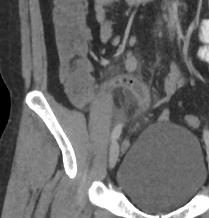

Se realiza búsqueda intencionada de la región de fosa iliaca derecha, apreciando una imagen tubular, en fondo de saco de ciego y presenta estriación de la grasa periapendicular la cual mide 10 mm en sentido anteroposterior, con presencia de un apendiculito en su interior de 5 mm, con densidad de 279 UH.